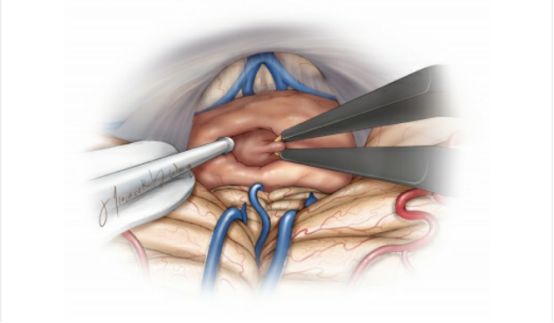

对于绝大部分松果体区肿瘤,笔者青睐于幕下小脑上(左侧)旁正中入路,这条入路通过沿着小脑幕面的下坡从侧方到达松果体区,提供了宽阔的手术通道,相对正中入路沿着小脑山顶进入,该入路能够触及位置更靠下方的肿瘤。

相对中线入路,该入路到达松果体区需离断的桥静脉更少,而且,从小脑幕面侧方的下坡进入可减少对小脑的强制性和固定牵拉。基于斜线的手术通道,使得对肿瘤对侧部分的显露充分许多,对于大型松果体区肿瘤的全切也更为轻松。但有时肿瘤与周围神经血管结构纤维性粘连,使切除程度受限。

图16. 图示为幕下小脑上(左侧)旁正中入路进入松果体区的手术通道。为了联合幕上入路,天幕可能被切开。但是这种间接的手术通道可能会使术者迷失方向。

图17. 图示为幕下小脑上(左侧)旁正中入路切除一例松果体母细胞瘤。注意上图左侧的滑车神经,小脑上动脉的分支被推开。下图所示旁正中入路显露肿瘤后极的包膜。